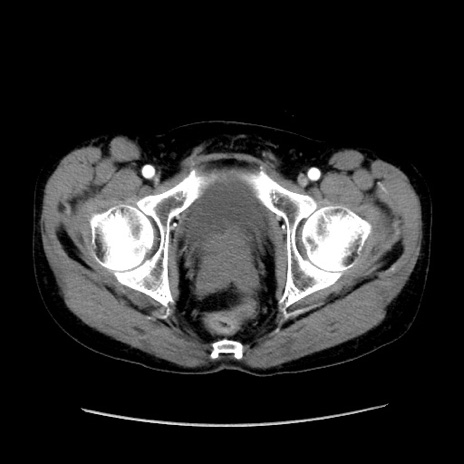

症例37(横断像)

【症例】40歳代 男性

【主訴】腹痛

【現病歴】4時間ほど前に電車に乗車中に臍部上より腹痛出現。徐々に増悪し起立困難となり、救急外来受診。生ものは数日食べていない。今朝お雑煮を食べた。

【身体所見】BT 36.8℃、BP 117/84mmHg、HR 91/min、SpO2 97%、苦悶様、腹部:臍上部広範囲圧痛あり、反跳痛±

【データ】WBC 8100、CRP 0.03